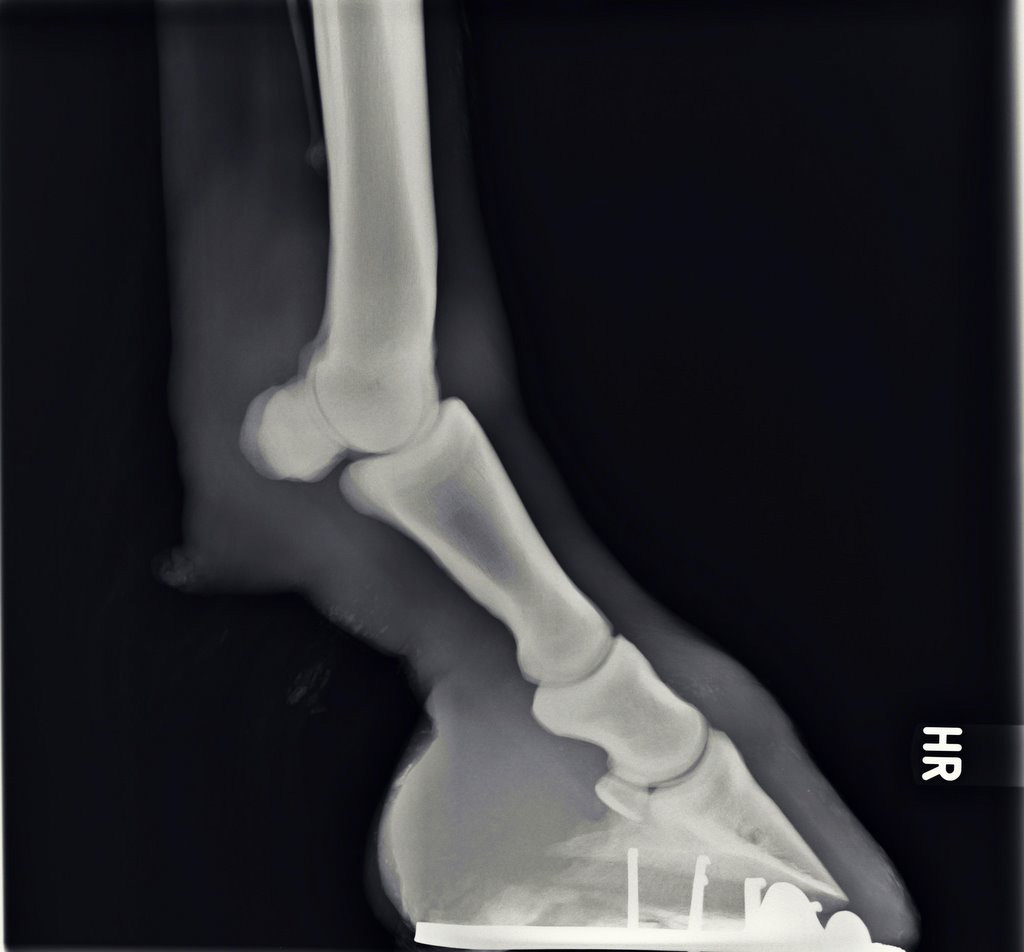

Illustrative Mindeststandardaufnahmen zur Beurteilung nach dem Röntgenleitfaden: